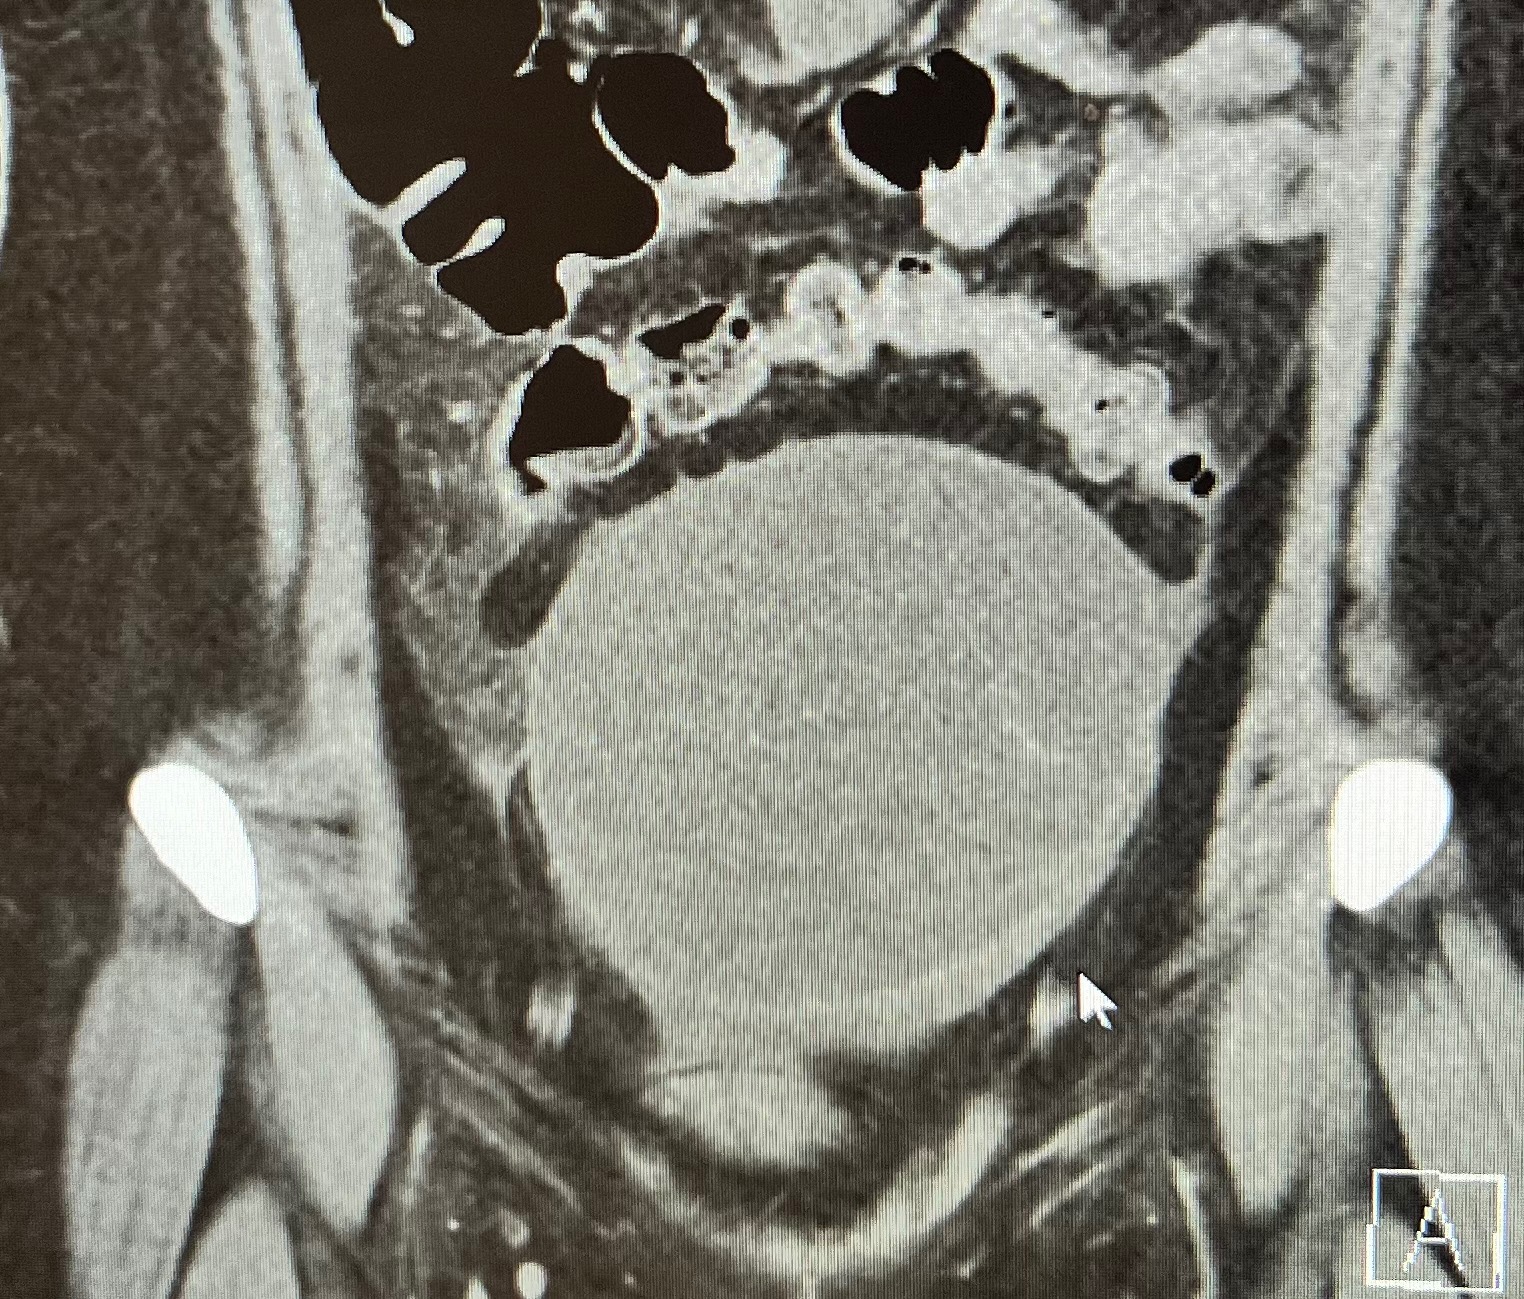

Over the past few months, I have been navigating some unexpected health challenges. I was diagnosed with a large pelvic mass on my left ovary that has continued to grow, along with an elevated CA-125 level. In October, I also experienced sepsis caused by a UTI, which doctors believe may have been related to the mass putting pressure on my bladder.

I have surgery scheduled for January 9th with a gynecologic oncologist, during which the mass will be removed along with my left ovary and left fallopian tube. Recovery is expected to take 6–8 weeks leaving me unable to work. Following surgery, I will also undergo additional testing to better understand the next steps in my care.